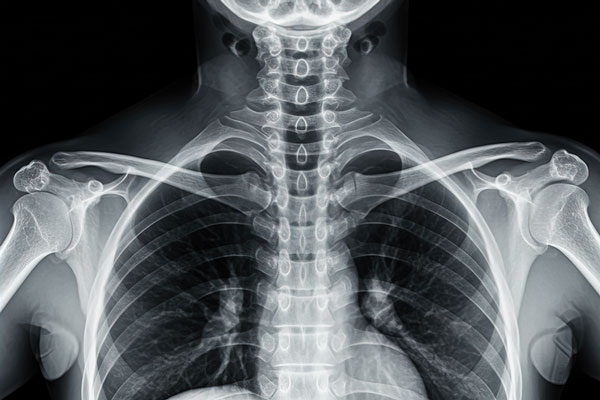

The type of imaging ordered depends on the suspected condition. X-rays are useful for detecting fractures, arthritis, and alignment problems. If soft tissue damage, disc herniations, or nerve compression is suspected, an MRI is the preferred option. A CT scan may be used when an MRI isn’t possible or when a more detailed view of the bones is needed.